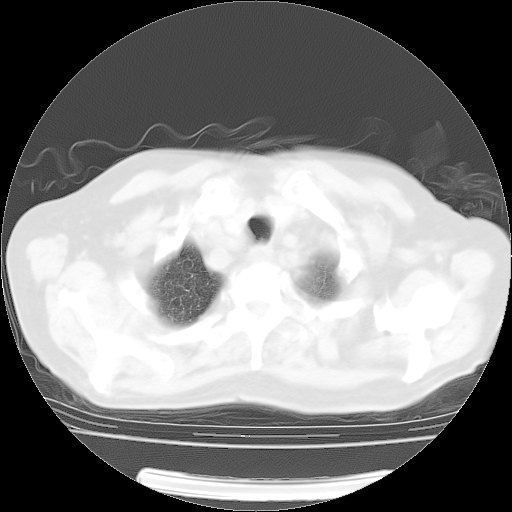

4月14日肺部CT

23.JPG

24.JPG

25.JPG

26.JPG

肺部CT平扫未见异常。